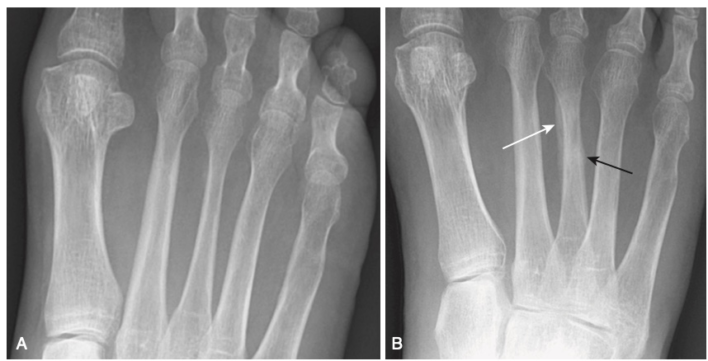

- Gãy Jones là một gãy ngang của xương bàn đốt chân ngón út cách nền xương khoảng 1 đến 2 cm, do gập lòng bàn chân và cổ chân vẹo trong. Gãy xương Jones thường lâu lành hơn so với gãy bong mảnh bám nền xương bàn đốt ngón chân út (là loại gãy thường gặp hơn, dancer’s fracture) (Hình 12).